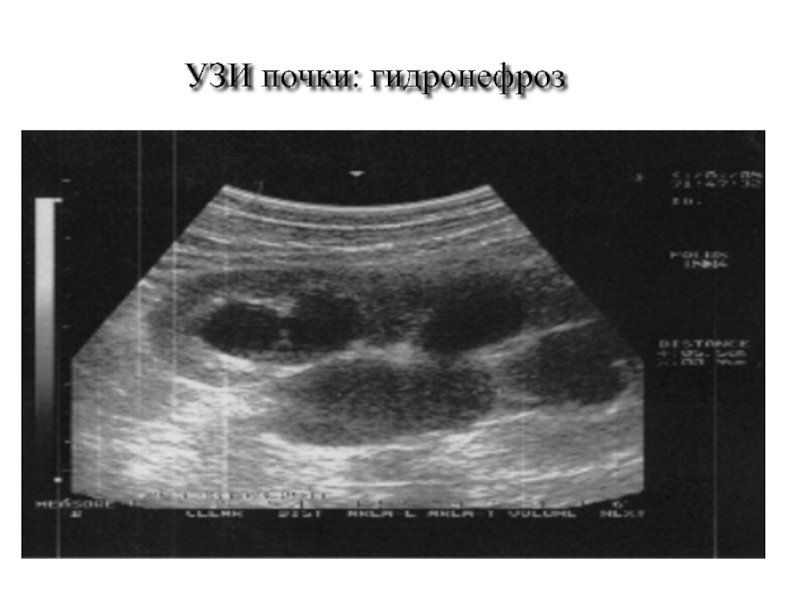

Слайд 60УЗИ почки: гидронефроз